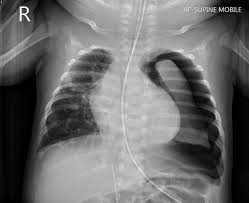

El paradigma del diagnóstico ha evolucionado de forma significativa. Aunque la radiografía de tórax sigue siendo el estándar inicial, el ultrasonido pulmonar a pie de cama (pocus) ha demostrado ser superior en la detección de neumotórax pequeños, especialmente frente a la radiografía en decúbito supino. El hallazgo del punto pulmonar mediante ecografía es un signo 100% específico, representando la frontera exacta entre el pulmón normal y el área colapsada. En casos de recurrencia, la tomografía computarizada se vuelve esencial, pero no de forma rutinaria en el primer episodio, reservándose principalmente para la planificación de la evaluación prequirúrgica.